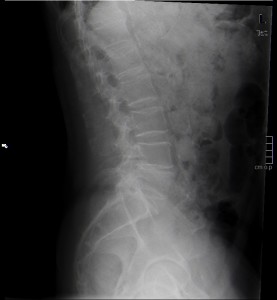

Caso 48

La opción correcta es la a), ya que el paciente acude por un cuadro de lumbalgia, por lo que hemos de estudiar las posibles alteraciones de la columna a este nivel susceptibles de causar esos síntomas y, al ser esto una primera prueba radiodiagnóstica, está indicada la radiografía de columna. A su vez, está indicada la placa de tórax por la condición de fumador importante del paciente, que podría tener un cáncer de pulmón que, de forma secundaria (metástasis) afectara a la columna del paciente.